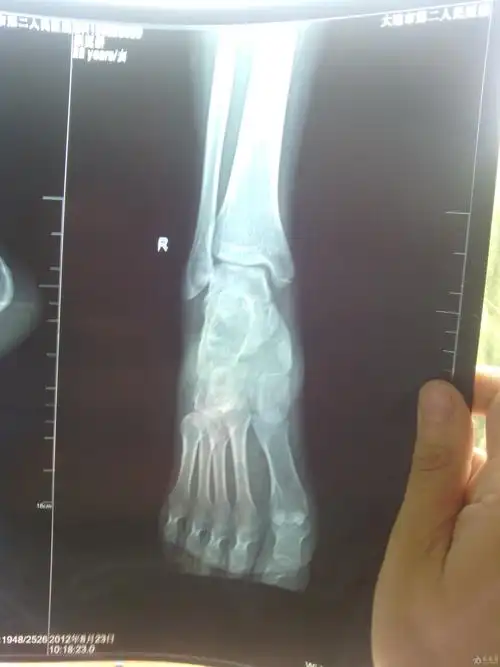

楔骨骨折